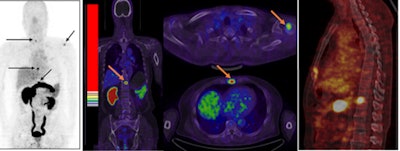

Ga-68 BBN-RGD PET/CT of a 64-year-old man with newly diagnosed prostate cancer shows multiple bone metastases (arrow). Image courtesy of JNM and Jingjing Zhang, Peking Union Medical College in Beijing.The results are better than scanning with a methylene diphosphonate (MDP) radiopharmaceutical, and no adverse side effects were found during the procedure and a two-week follow-up.

The study included four patients who were newly diagnosed with prostate cancer, nine patients who had received therapy, and five healthy volunteers. Ga-68 BBN-RGD PET/CT detected 20 bone lesions in seven patients either with primary prostate cancer or after radical prostatectomy.